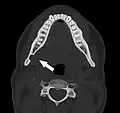

Stafne bone cavity seen on coronal CT

Stafne bone cavity seen on axial CT